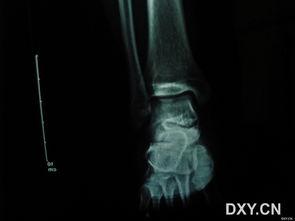

视频接着展示了医生对男子进行诊断的过程。医生首先询问了男子的受伤经过,然后仔细观察了他的小腿。在确认了骨折的位置后,医生用X光片进一步确认了骨折的程度。这一环节让我们看到了医生的专业素养和严谨的工作态度。